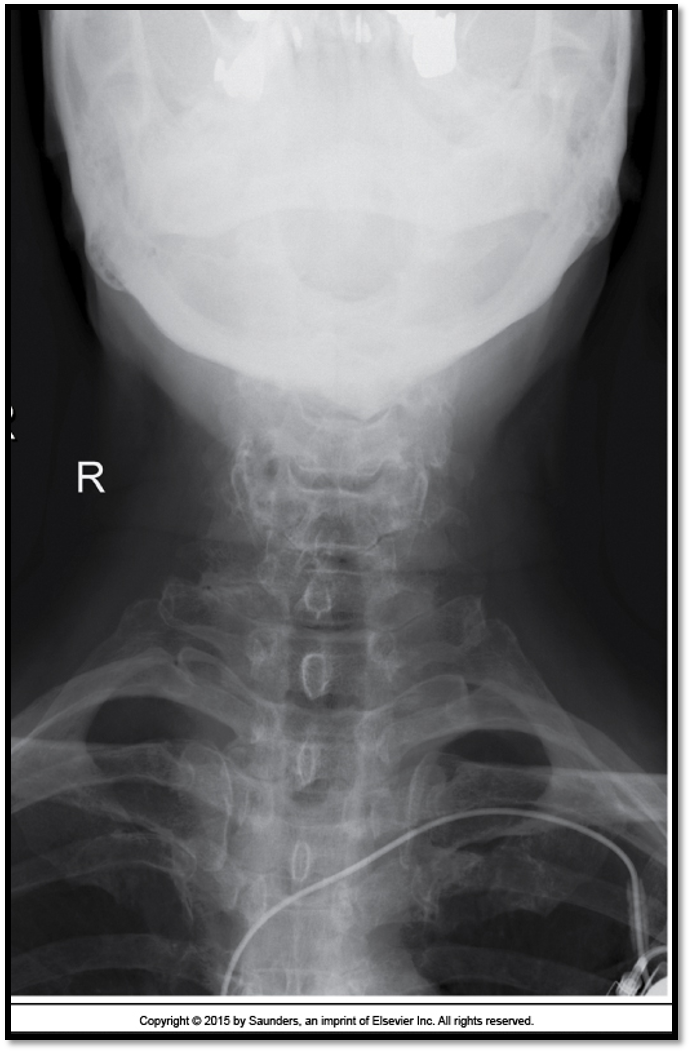

AP Axial Cspine criteria

A

• occipital bone and mandible lined up (extension)

• spinous process midline (rotation)

• open vertebral discs (angle)

• all of C3 is visible

• need to lift the chin more

• all of C3 is demonstrated